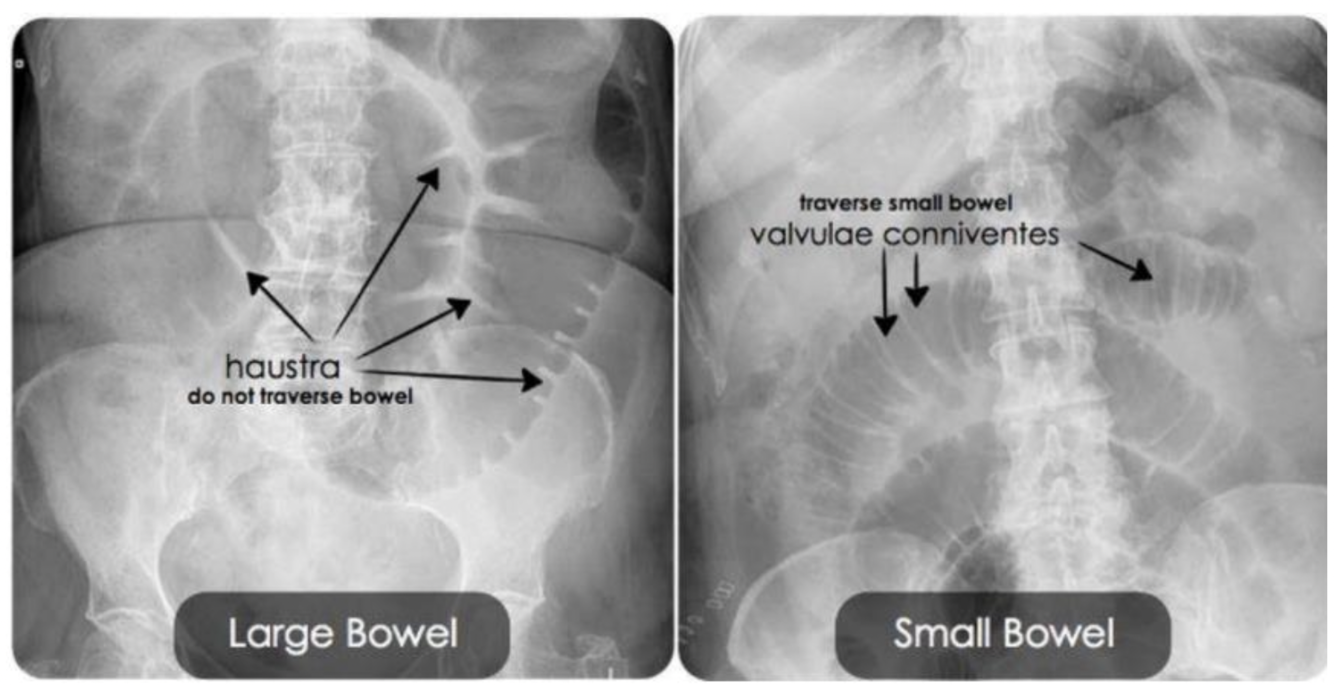

איך מבדילים בין המעי הדק לגס בצילומי בטן?

המעי הגס הוא פריפרי ויש לו האוסטרות, הן לא חוצות את כל המעי לרוחב.

במעי הדק לעומת זאת רואים פסים לבנים שחוצים את המעי מדופן לדופן.